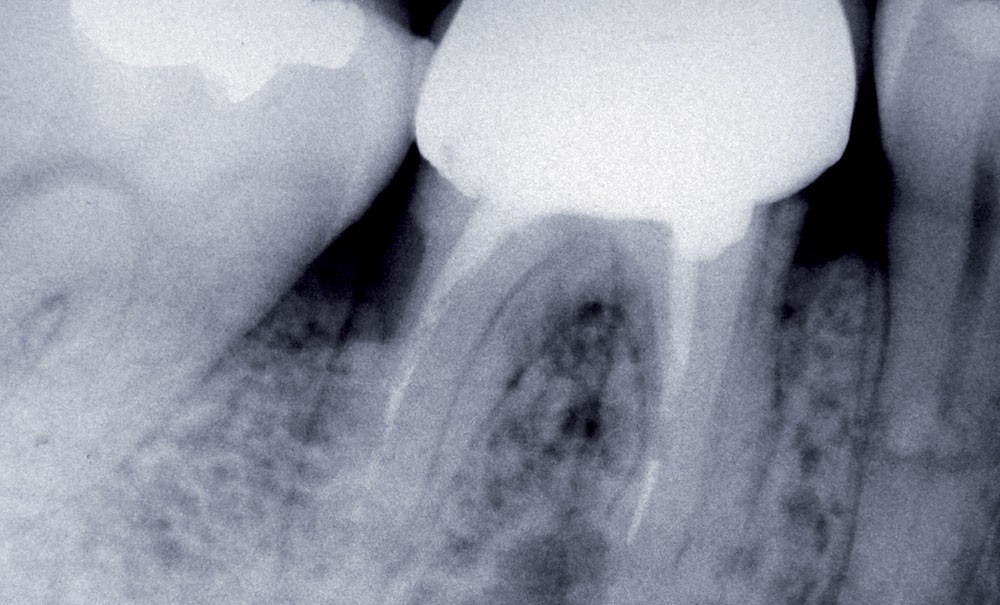

En revanche, l’assureur alerte pour la deuxième année consécutive sur une hausse de la sinistralité en endodontie : complications sous prothèse conjointe pour infections apicales liées au traitement préprothétique réalisé ou à l’état initial insuffisant non repris, bris d’instruments ou non-conformité de l’obturation à terme sans réalisation de prothèse, faux canaux et perforations radiculaires, dépassements apicaux… « Le domaine endodontique reste l’un des postes les plus à risque de réclamation, souligne le rapport. En reprenant les allégations d’insuffisances en analyse transversale, nous obtenons un global de 513 déclarations. Sans comptabiliser les 5 ingestions ni l’inhalation d’instrument endodontique… »

L’essentiel des litiges porte sur la prothèse (56 %). Leur nombre est en légère hausse, avec 722 dossiers contre 667 en 2017. En tête du palmarès comme toujours : la prothèse fixée (couronne, bridge, inlay, onlay) avec 551 déclarations dont 221 relatives à des soins endodontiques préprothétiques non conformes (ou non repris) : perforation (32 cas), bris instrumentaux (27), obturation canalaire non conforme (162), lésion apicale… À noter également, 192 litiges portant sur des restaurations techniquement inadaptées : insuffisance de point de contact, équilibration occlusale ou étanchéité périphérique, reprises de carie sous restauration, descellements… En prothèses amovibles et mixtes, on dénombre 137 dossiers.

Le deuxième groupe d’importance par le volume des déclarations (35 % des litiges hors implantologie) est celui des « complications diverses suite à des actes de soins et de chirurgie » (446 dossiers versus 419 en 2017). Les complications endodontiques représentent 55 % de cet ensemble avec 247 déclarations dont 220 pour bris d’instrumentation, ce qui correspond à une hausse de 91 dossiers par rapport à 2017 et de 162 dossiers par rapport à 2016, soit une augmentation de 19 % en deux ans.